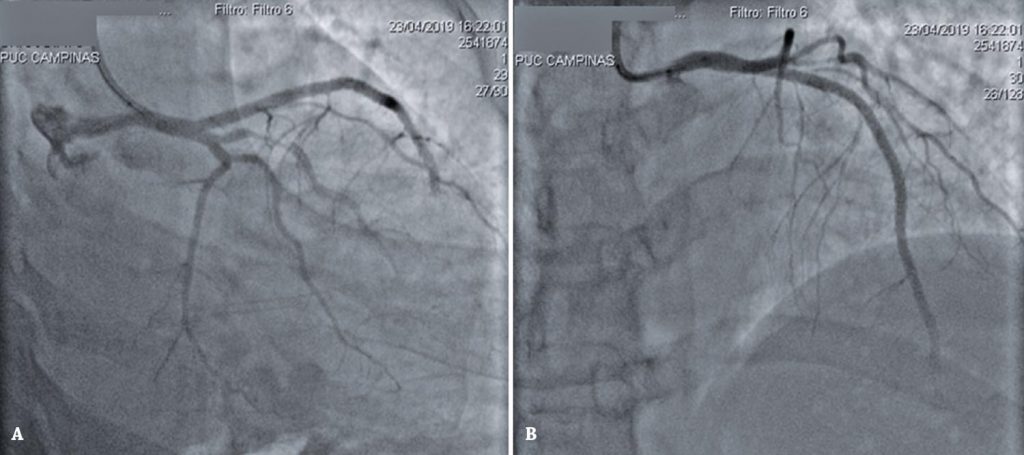

Figure 4

Coronary angiography showing the result of the procedure. (A) Right anterior oblique caudal view shows marginal branch dissection, maintained under conservative treatment. (B) In a right anterior oblique cranial projection, three stents are observed in the left anterior descending artery, with no opacification of the distal bed of this coronary vessel.